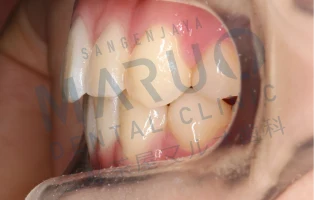

06.三軒茶屋マルオ歯科矯正担当医の治療例

症例1

治療前

治療中

動的治療終了時

| 主訴 | 上の前歯が前に出ている 歯のでこぼこ |

|---|---|

| 診断名 | 上顎前突 叢生 |

| 年齢 | 13歳 |

| 治療に用いた主な装置 | マルチブラケット装置 |

| 抜歯部位 | 上下両側第一小臼歯 |

| 治療期間 | 2年6ヶ月 |

| 治療費 | 92万4,000円(税込) |

| リスク、副作用 | むし歯や歯周病、歯根吸収、治療後の後戻りの可能性があります |